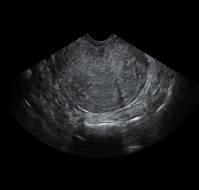

Ovarian torsion is a gynecological emergency caused by rotation of the ovary on its supporting ligaments, leading to compromised blood flow and potential ovarian nec..

Clinical PresentationAn eleven-year-old premenarcheal girl presented with acute lower left abdominal pain and vomiting. On examination, her vital signs were stable, ..